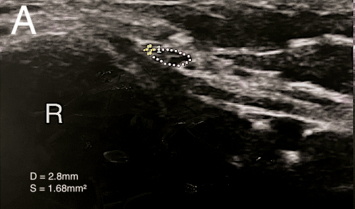

DOI: 10.7759/cureus.88503 정상적인 왼쪽 팔의 신경 (A) 단면적은 1.68mm²였는데,